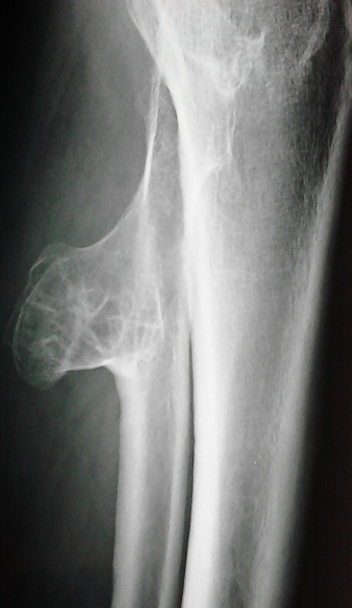

Les exostoses représentent la forme la plus fréquente des tumeurs osseuses bénignes, elles peuvent être uniques ou multiples se formant au niveau des métaphyses des os longs avec une prédilection pour le fémur et l'humérus. Elles sont le plus souvent asymptomatiques mais peuvent parfois être révélées par une complication osseuse ou à l'occasion de la compression de tissus mous de voisinage. Les compressions vasculaires sont plus rares. Patient âgé de 45 ans était hospitalisé pour un bilan étiologique d'une embolie pulmonaire. L'échographie doppler veineuse des membres inférieurs concluait à une thrombose veineuse profonde. Un bilan étiologique exhaustif était sans anomalies. L'examen clinique était normal en dehors d'une masse dure d'environ 10cm de grand axe du mollet gauche avec diminution du ballottement. La radiographie des jambes notait une excroissance osseuse ovalaire et bien limitée de la partie proximale du péroné gauche. Plusieurs diagnostics ont été évoqués notamment un chondrome sous périosté vieilli, un sarcome parostéal et une dysplasie épiphysaire hémimélique. Les radiographies du bassin et des fémurs étaient sans anomalies. L'échographie des parties molles confirmait la nature osseuse de cette excroissance et excluait une anomalie musculaire associée. Les caractéristiques radiologiques de la masse à savoir une néoformation osseuse dont la corticale est en continuité avec la corticale de l'os sous jacent était en faveur d'une exostose ou ostéochondrome. Etant donné le caractère symptomatique de cette exostose, une exérèse chirurgicale a été indiquée.